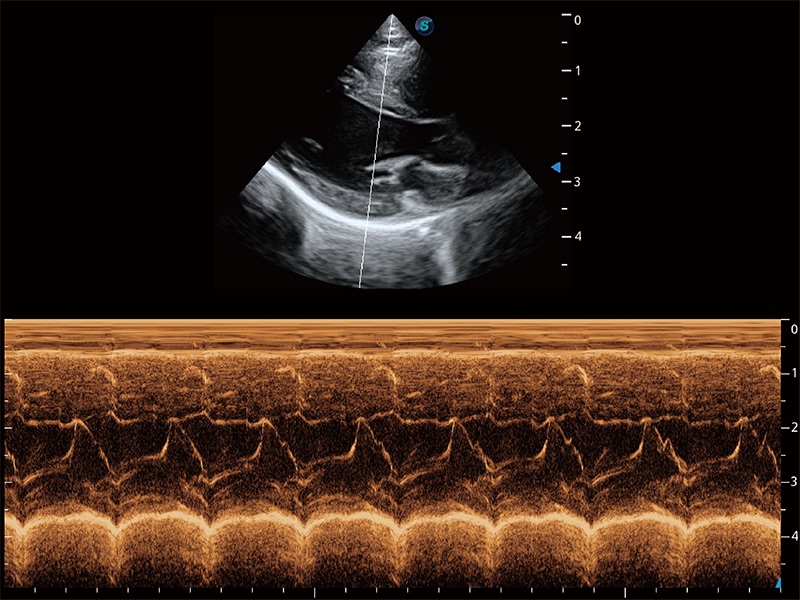

ProPet 80 配備了豐富的心臟探頭群、先進(jìn)的成像技術(shù)和專業(yè)的心臟測量工具,可幫助動物醫(yī)生為不同體型和生理結(jié)構(gòu)的動物提供心臟和心肌功能的全面評估。

通過360度任意調(diào)節(jié)3條M型取樣線,在同一心動周期上觀察心臟不同位置的運(yùn)動曲線,得到準(zhǔn)確的心功能測量數(shù)據(jù),有效評估心肌運(yùn)動及左心室功能。

實時用顏色表示心肌組織運(yùn)動,觀察和定量組織的運(yùn)動情況,對快速檢測與評估心肌的灌注和活性、電傳導(dǎo)及心肌收縮和舒張功能等均能提供重要的診斷信息。